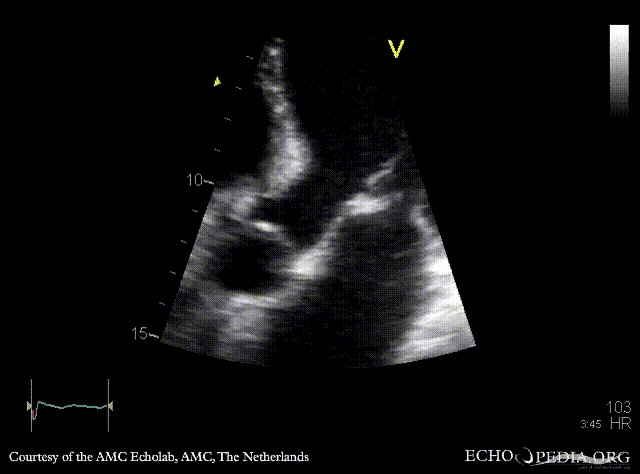

Endocarditis of mitral valve

A3CH: Color doppler, severe mitral regurgitation Continuous-wave signal of tricuspid regurgitation, increased SPAP